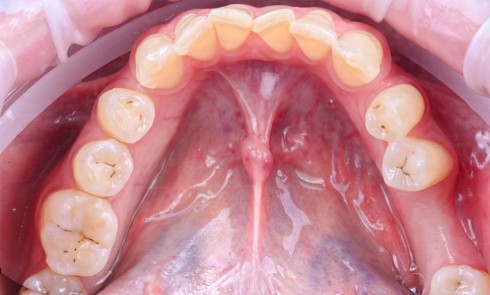

La perte d’une ou plusieurs dents entraîne la perte des points de contact, responsables de la stabilité et de la continuité de l’arcade. Par conséquent, une avulsion a pour première conséquence la migration ou la version d’une ou plusieurs dents distales (fig. 1 et 2). Cela est vrai en antérieur comme en postérieur.

Cette version, quand elle se produit, modifie les espaces interdentaires et complique l’hygiène proximale des patients. Des caries peuvent alors se développer en interproximal sans que cela soit forcément visible à l’examen visuel (fig. 3 et 4). Les radios de type bite-wing (rétro-coronaires) prennent alors tout leur sens (fig. 5 et 6).

Des conséquences sur l’arcade antagoniste s’ajoutent à toutes les perturbations de l’arcade concernée. La dent antagoniste à l’édentement n’est plus calée et peut par conséquent s’égresser. Cette égression modifie les points de contact et les espaces interdentaires, pouvant conduire à des tassements alimentaires et des caries secondaires [18, 19].